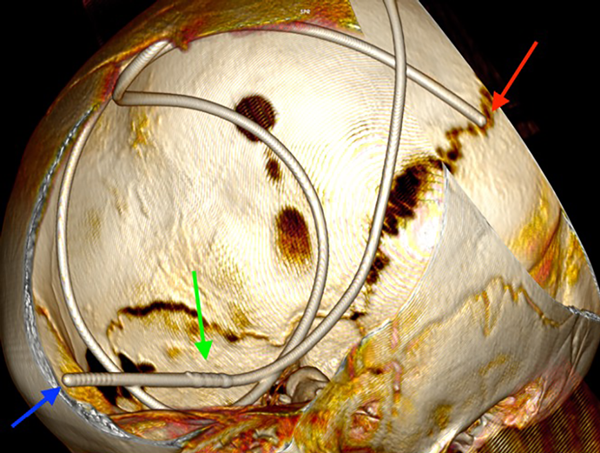

En las siguientes 2 semanas la paciente presentó cefalea de manera progresiva más deterioro del nivel de conciencia y vómitos, por lo que se indicó TC y radiografía de control, en estas se observó el catéter de derivación dentro del espacio subdural en su totalidad debido a migración cefálica completa (Figuras 1 a 3).

Figura 3. Reconstrucción 3D de tomografía computarizada. Se observa el catéter de derivación subduroperitoneal en localización intracraneana completa luego de ocurrir la migración cefálica. Se logran visualizar ambos extremos (flecha roja el proximal, flecha azul el distal) y el conector recto (flecha verde).